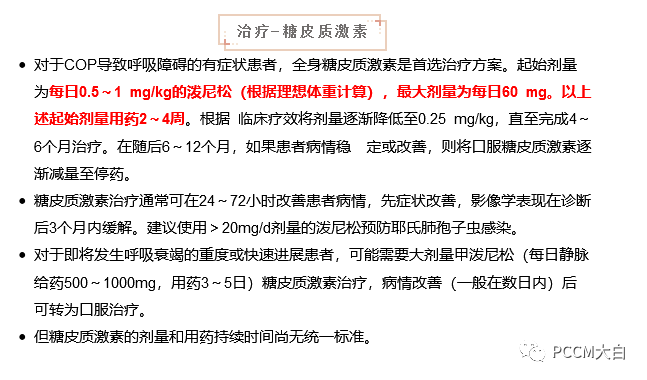

少数COP患者可自行缓解,对于一些无症状或症状轻微的COP患者,单纯使用大环内酯类药物如克拉霉素、红霉素治疗后症状即可改善。激素是目前治疗COP的主要措施,临床症状一般在48h内得到改善,影像学病变常常在几天内明显吸收。激素治疗原则是早期、足量、足疗程,以减少并发症,降低复发率和病死率。激素起始用量,泼尼松60mg/d或0.75~1mg/(kg·d),时间1~3个月,逐渐减量至20~40mg,时间为3个月,维持剂量为泼尼松5~10mg/d,后期可改为泼尼松5mg,隔日1次。

对急性进展型COP可选择甲泼尼龙500~1000mg/d静脉冲击治疗,连用3~5天,随后改为泼尼松1mg/(kg·d)口服。65%~80%的患者予激素治疗可收到良好效果,甚至可以获得完全缓解,仅少数患者应用激素治疗后病情继续进展,最终因呼吸衰竭死亡。应用激素治疗COP的另一个特点是停药或减量过程中容易复发,常发生在激素停用或减量后3个月内。延迟治疗和治疗维持时间过短是COP复发的常见原因。如对激素反应欠佳,需要采取其他的治疗方法,如细胞毒药物(环磷酰胺、硫唑嘌呤等),但其疗效难以评估。